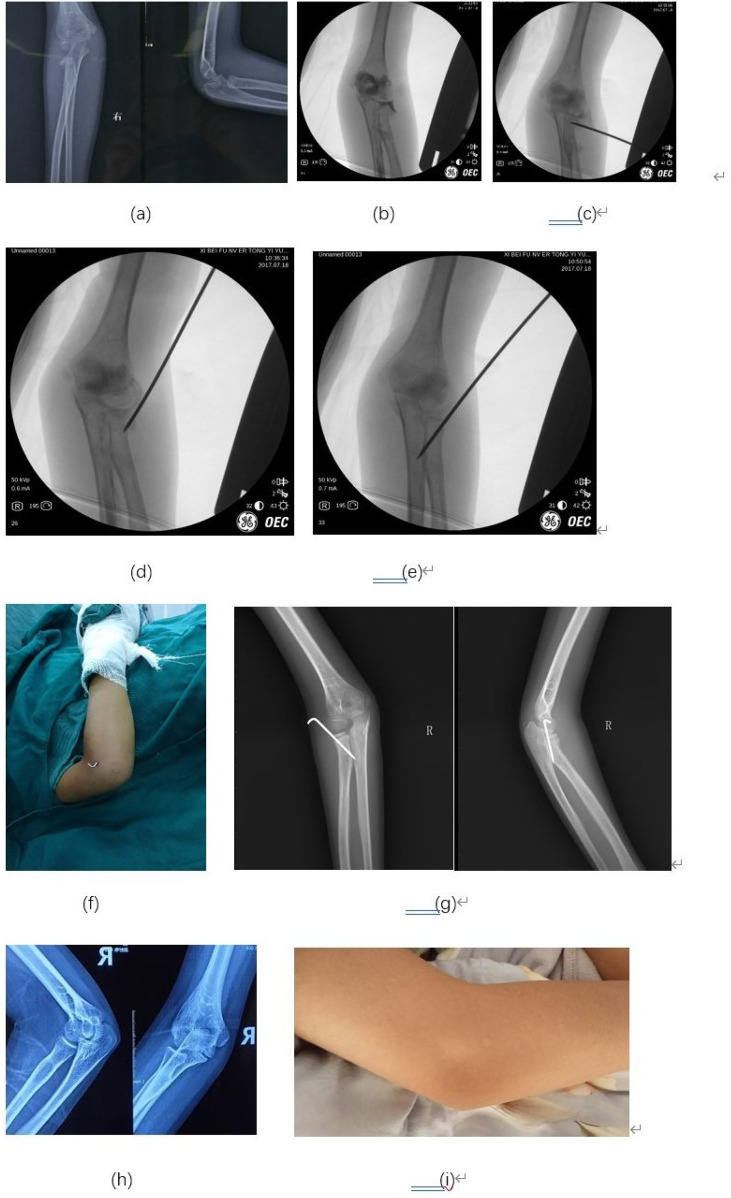

{"title":"经皮克氏针复位配合肘关节摄影治疗儿童桡骨颈骨折。","authors":"Hai Jiang, Tao Li","doi":"10.3389/fped.2025.1571774","DOIUrl":null,"url":null,"abstract":"<p><strong>Objective: </strong>Radial neck fractures in children can easily become complicated if not managed properly. Percutaneous reduction using the leverage technique with or without internal fixation with a Kirschner wire (K-wire) is a minimally invasive approach for treating angulated radial neck fractures in children. The study aims to evaluate the radiological and clinical outcomes of percutaneous leverage reduction assisted by elbow arthrography for pediatric radial neck fractures.</p><p><strong>Methods: </strong>From January 2016 to June 2020, we treated 47 children with angulated radial neck fractures, including 35 boys and 12 girls. The patient's age ranged from 2 to 13 years, with an average age of 6 years 9 months. According to Judet classification, 21 cases were classified as Type III, 15 cases as Type IVa and 11 cases as Type IVb. To overcome the difficulty of reduction caused by the absence of the ossified radial head centers in young children, we used intraoperative elbow arthrography to assist with the reduction. After achieving satisfactory reduction, one or two K-wires were inserted percutaneously to fix the fracture site and prevent reduction loss.</p><p><strong>Results: </strong>All cases were followed up for an average of 43 months, ranging from 24 months to 90 months. No radial head necrosis or synostosis of the proximal ulna and radius was observed during the long-term follow-up. No epiphyseal arrest or valgus of the elbow was noted at the end of the follow-up. According to the Metaizeau reduction classification, 42 cases were rated excellent, and 5 cases as good. Based on the Metaizeau clinical classification, 45 cases were excellent and 2 were good.</p><p><strong>Conclusion: </strong>Closed reduction assisted by intraoperative elbow arthrography, combined with percutaneous leverage technique and internal fixation with K-wires, achieved satisfactory reduction and functional outcomes in children with angulated radial neck fractures, even in cases where the radial head ossification centers were not yet visible.</p>","PeriodicalId":12637,"journal":{"name":"Frontiers in Pediatrics","volume":"13 ","pages":"1571774"},"PeriodicalIF":2.0000,"publicationDate":"2025-09-19","publicationTypes":"Journal Article","fieldsOfStudy":null,"isOpenAccess":false,"openAccessPdf":"https://www.ncbi.nlm.nih.gov/pmc/articles/PMC12491315/pdf/","citationCount":"0","resultStr":"{\"title\":\"Percutaneous leverage reduction with kirschner-wire fixation assisted by elbow arthrography for pediatric radial neck fractures.\",\"authors\":\"Hai Jiang, Tao Li\",\"doi\":\"10.3389/fped.2025.1571774\",\"DOIUrl\":null,\"url\":null,\"abstract\":\"<p><strong>Objective: </strong>Radial neck fractures in children can easily become complicated if not managed properly. Percutaneous reduction using the leverage technique with or without internal fixation with a Kirschner wire (K-wire) is a minimally invasive approach for treating angulated radial neck fractures in children. The study aims to evaluate the radiological and clinical outcomes of percutaneous leverage reduction assisted by elbow arthrography for pediatric radial neck fractures.</p><p><strong>Methods: </strong>From January 2016 to June 2020, we treated 47 children with angulated radial neck fractures, including 35 boys and 12 girls. The patient's age ranged from 2 to 13 years, with an average age of 6 years 9 months. According to Judet classification, 21 cases were classified as Type III, 15 cases as Type IVa and 11 cases as Type IVb. To overcome the difficulty of reduction caused by the absence of the ossified radial head centers in young children, we used intraoperative elbow arthrography to assist with the reduction. After achieving satisfactory reduction, one or two K-wires were inserted percutaneously to fix the fracture site and prevent reduction loss.</p><p><strong>Results: </strong>All cases were followed up for an average of 43 months, ranging from 24 months to 90 months. No radial head necrosis or synostosis of the proximal ulna and radius was observed during the long-term follow-up. No epiphyseal arrest or valgus of the elbow was noted at the end of the follow-up. According to the Metaizeau reduction classification, 42 cases were rated excellent, and 5 cases as good. Based on the Metaizeau clinical classification, 45 cases were excellent and 2 were good.</p><p><strong>Conclusion: </strong>Closed reduction assisted by intraoperative elbow arthrography, combined with percutaneous leverage technique and internal fixation with K-wires, achieved satisfactory reduction and functional outcomes in children with angulated radial neck fractures, even in cases where the radial head ossification centers were not yet visible.</p>\",\"PeriodicalId\":12637,\"journal\":{\"name\":\"Frontiers in Pediatrics\",\"volume\":\"13 \",\"pages\":\"1571774\"},\"PeriodicalIF\":2.0000,\"publicationDate\":\"2025-09-19\",\"publicationTypes\":\"Journal Article\",\"fieldsOfStudy\":null,\"isOpenAccess\":false,\"openAccessPdf\":\"https://www.ncbi.nlm.nih.gov/pmc/articles/PMC12491315/pdf/\",\"citationCount\":\"0\",\"resultStr\":null,\"platform\":\"Semanticscholar\",\"paperid\":null,\"PeriodicalName\":\"Frontiers in Pediatrics\",\"FirstCategoryId\":\"3\",\"ListUrlMain\":\"https://doi.org/10.3389/fped.2025.1571774\",\"RegionNum\":3,\"RegionCategory\":\"医学\",\"ArticlePicture\":[],\"TitleCN\":null,\"AbstractTextCN\":null,\"PMCID\":null,\"EPubDate\":\"2025/1/1 0:00:00\",\"PubModel\":\"eCollection\",\"JCR\":\"Q2\",\"JCRName\":\"PEDIATRICS\",\"Score\":null,\"Total\":0}","platform":"Semanticscholar","paperid":null,"PeriodicalName":"Frontiers in Pediatrics","FirstCategoryId":"3","ListUrlMain":"https://doi.org/10.3389/fped.2025.1571774","RegionNum":3,"RegionCategory":"医学","ArticlePicture":[],"TitleCN":null,"AbstractTextCN":null,"PMCID":null,"EPubDate":"2025/1/1 0:00:00","PubModel":"eCollection","JCR":"Q2","JCRName":"PEDIATRICS","Score":null,"Total":0}

目的:儿童桡骨颈骨折如果处理不当,很容易变得复杂。采用克氏针(k -丝)内固定或不内固定经皮杠杆复位技术是治疗儿童桡骨颈角骨折的一种微创方法。本研究旨在评估经皮肘关节造影辅助下杠杆复位治疗儿童桡骨颈骨折的放射学和临床效果。方法:2016年1月至2020年6月,对47例儿童桡骨颈角骨折进行治疗,其中男孩35例,女孩12例。患者年龄2 ~ 13岁,平均年龄6岁9个月。其中,ⅲ型21例,IVa型15例,IVb型11例。为了克服由于幼童桡骨头中心骨化缺失导致复位困难,我们采用术中肘关节摄影辅助复位。复位满意后,经皮插入一至两根克氏针固定骨折部位,防止复位损失。结果:所有病例平均随访43个月,随访时间从24个月到90个月不等。在长期随访期间,未观察到桡骨头坏死或近端尺骨和桡骨缝闭塞。随访结束时未发现骨骺停止或肘关节外翻。根据Metaizeau还原分级,优42例,良5例。根据Metaizeau临床分型,优45例,良2例。结论:术中肘关节造影辅助下的闭合复位,结合经皮杠杆技术和克氏针内固定,即使在桡骨头骨化中心尚未可见的情况下,对成角型桡骨颈骨折的儿童也取得了满意的复位和功能效果。

Methods: From January 2016 to June 2020, we treated 47 children with angulated radial neck fractures, including 35 boys and 12 girls. The patient's age ranged from 2 to 13 years, with an average age of 6 years 9 months. According to Judet classification, 21 cases were classified as Type III, 15 cases as Type IVa and 11 cases as Type IVb. To overcome the difficulty of reduction caused by the absence of the ossified radial head centers in young children, we used intraoperative elbow arthrography to assist with the reduction. After achieving satisfactory reduction, one or two K-wires were inserted percutaneously to fix the fracture site and prevent reduction loss.